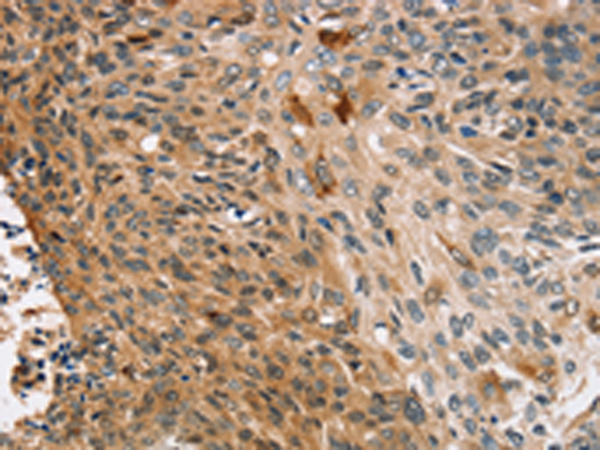

分类: 科研抗体货号: P10729别名: CASP-12, CASP12P1应用: WB,IHC反应种属: Human, Mouse

分类: 科研抗体货号: P10708别名: ASH1; HASH1; MASH1; bHLHa46应用: IHC反应种属: Human, Mouse, Rat

分类: 科研抗体货号: P10727别名: FAD, FACD, FAD1, GLM3, BRCC2, FANCB, FANCD, PNCA2, FANCD1, BROVCA2应用: IHC反应种属: Human

分类: 科研抗体货号: P10745别名: CEA cell adhesion molecule 5,CEA, CD66e应用: IHC反应种属: Human

分类: 科研抗体货号: P10725别名: BNP; Iso-ANP应用: IHC反应种属: Human

分类: 科研抗体货号: P10743别名: CDC18L; HsCDC6; MGORS5; HsCDC18应用: WB,IHC反应种属: Human

分类: 科研抗体货号: P10723别名: KGF; HBGF-7应用: IHC反应种属: Human, Mouse, Rat

分类: 科研抗体货号: P10742别名: P50CDC37应用: WB,IHC反应种属: Human, Mouse, Rat

分类: 科研抗体货号: P10763别名: CNCG, CNG1, RP49, CNCG1, CNG-1, RCNC1, RCNCa, RCNCalpha应用: IHC反应种属: Human

分类: 科研抗体货号: P10741别名: BLR2, EBI1, CD197, CDw197, CMKBR7应用: WB反应种属: Human